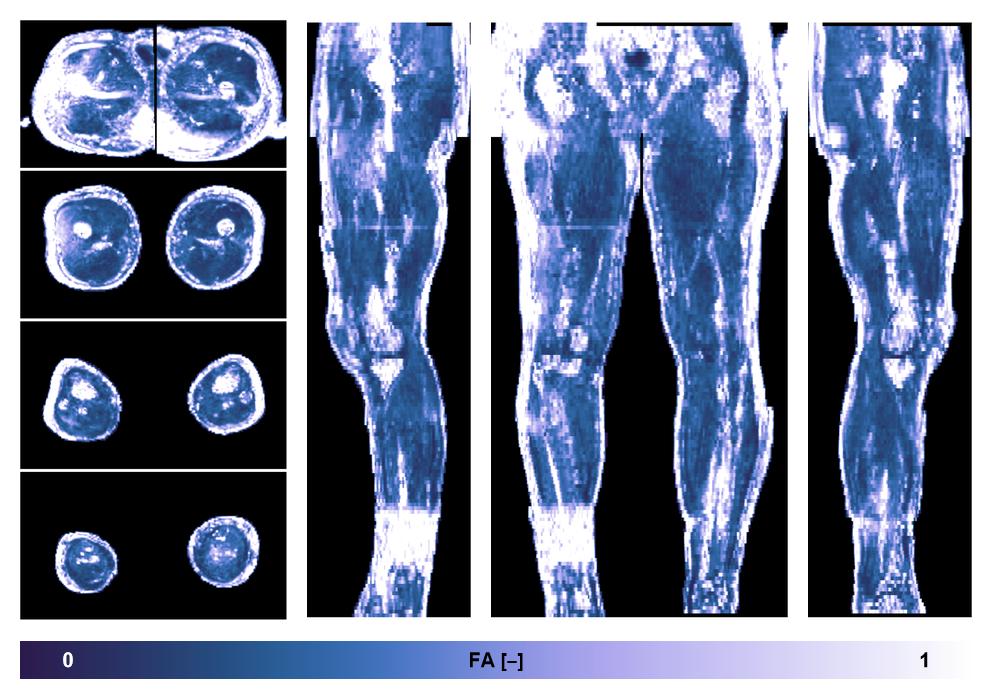

• Fractional anisotropy

IVIM corrected whole leg muscle fractional anisotropy obtained from diffusion tensor imaging.